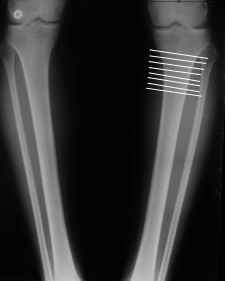

Вот ещё картинки, которые отправлял в Ортопод. Коррекция кривизны и удлинение на 3 см.

Мне представляется оптимальным на уровне 3-4 линии (т.е. как раз посредине отмеченной зоны). Если рассчимтываешь делать медиализацию, то параллельно суставной поверхности, иначе просто не сдвинешь без джистракции - отломки зацепятся. Если без медиализации - то вообще не имеет значения.

4. Если внимательно посмотришь на рентгенограммы, то в зоне перелома малоберцовой кости она втягиваетсмя внутрь, таким образом немного уменьшая объем тканей по внутреннему контуру. Причем чем выше - тем эффектнее. Не надо только совсем высоко лезть - там перонеус. Многих пайциенток это тоже смущает. Так что решаем проблему комплексно. На это, кстати, особо упирает Казбек Кудзаев.